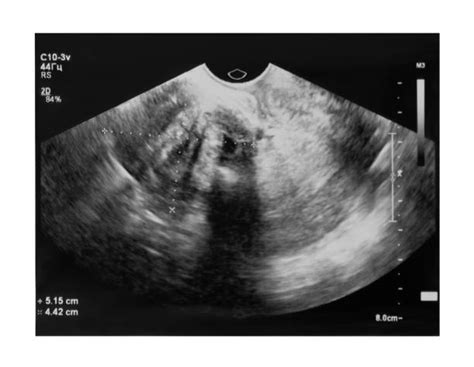

Výber počiatočnej zobrazovacej metódy závisí od veku pacientky a klinického scenára. Pred dosiahnutím veku 30 rokov je zvyčajne prvou voľbou ultrazvukové vyšetrenie. U žien vo veku 30 - 39 rokov sa uprednostňuje ultrazvuk, prípadne doplnený o diagnostickú mamografiu. Od veku 40 rokov sa diagnostická mamografia s cieleným ultrazvukom považuje za štandard pre symptomatické uzlíky.

Na základe rádiografického obrazu sú opísané typické znaky benígneho ochorenia: oválny tvar, paralelné usporiadanie, hladké kontúry a jednotná echostruktúra na ultrazvuku. „Atypické“ nálezy si však vyžadujú opatrnosť a v prípade nezhody s klinickým obrazom aj morfologické overenie. Na morfologickej úrovni sa rozlišujú varianty s prevahou stromálnej alebo duktálnej zložky. Táto hranica tvorí diagnostickú „sivú zónu“ s fyloidným nádorom, kde sa konečný záver robí na základe kombinácie znakov a klinického kontextu. Stanovenie štádia, ako je to bežné pri onkologických ochoreniach, sa na fibroadenóm neuplatňuje, pretože ide o benígny proces. Primárnou osou rozhodovania je pomer rizika a prínosu intervencie, nie štádium.